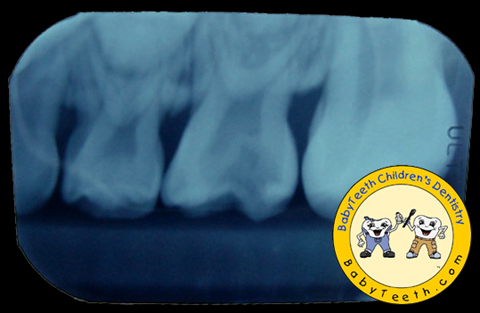

Radiographs taken after treatment.

Decay Removal & Pulpotomy

Decay has been removed

and pulpotomy performed.